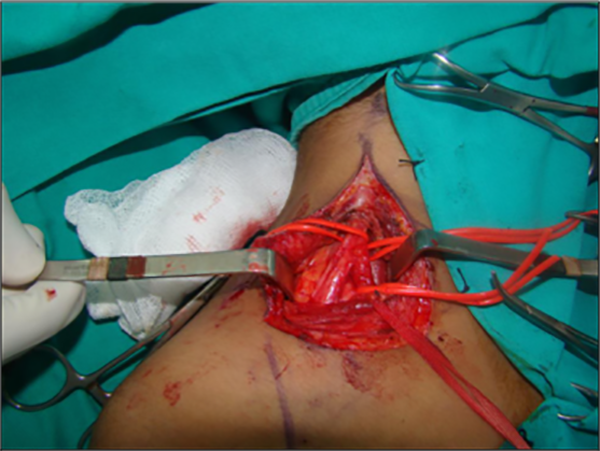

Se realiza abordaje del plexo braquial supra clavicular (foto 3) en el que se identifica tumoración ósea que comprime las raíces inferiores del plexo braquial a nivel supraclavicular.

Foto 3. Abordaje del plexo braquial a nivel supraclavicular. Identificación del tronco primario superior y sus divisiones.